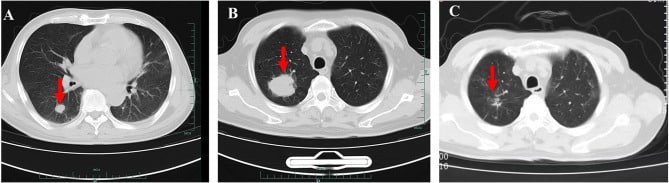

Chest CT of the patient (July 2023 in (A) picture, September 2023 in (B) picture, November 2023 in (C) picture, red arrows indicate pulmonary mass shadow).

While we still have the #1 Babesia Hematology identification book, this is lovely imaging but very dangerous with over 25% of the red blood cells infected. Typically, diagnosing such patients takes significant time, partly because medical training provides minimal instruction, and infection specialists receive very trivial education.